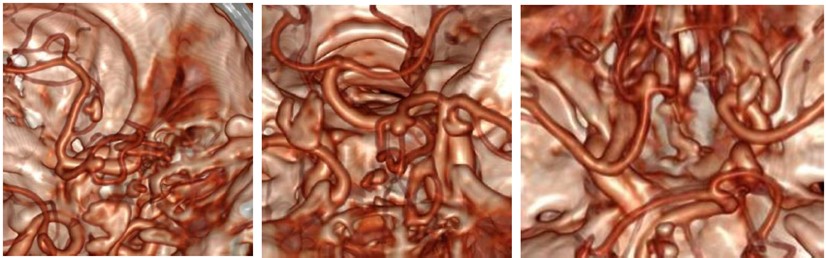

During surgery, the patient was placed in supine position with a neutral position of the head. A three-point fixation system and neuro-navigation system (BrainLab) were used. A bicoronal incision with bifrontal craniectomy were performed, using a subfrontal corridor for the tumor resection. Conventional microsurgery techniques were applied for initial tumor resection in its frontal extension; further dissection was carried out following anatomic landmarks until finding the arterial anterior communicating complex and the optic nerves surrounded by tumor. Careful dissection was then performed for the liberation of the optic apparatus continuing with the tumor resection between the quiasma and the AcommA (Figure 2). During this step a superior projection AcommA aneurysm was identified inside the solid central part of the tumor (video/imagen). After delimitation simultaneous tumor resection and dissection of the aneurysm was performed in order to clip it. After complete liberation of the aneurysm a 5 mm fenestrated clip was located in the neck of the lesion corroborating afterwards its complete occlusion using fluorescein. Haemostasis was confirmed, and closure was performed conventionally (Figure 3).